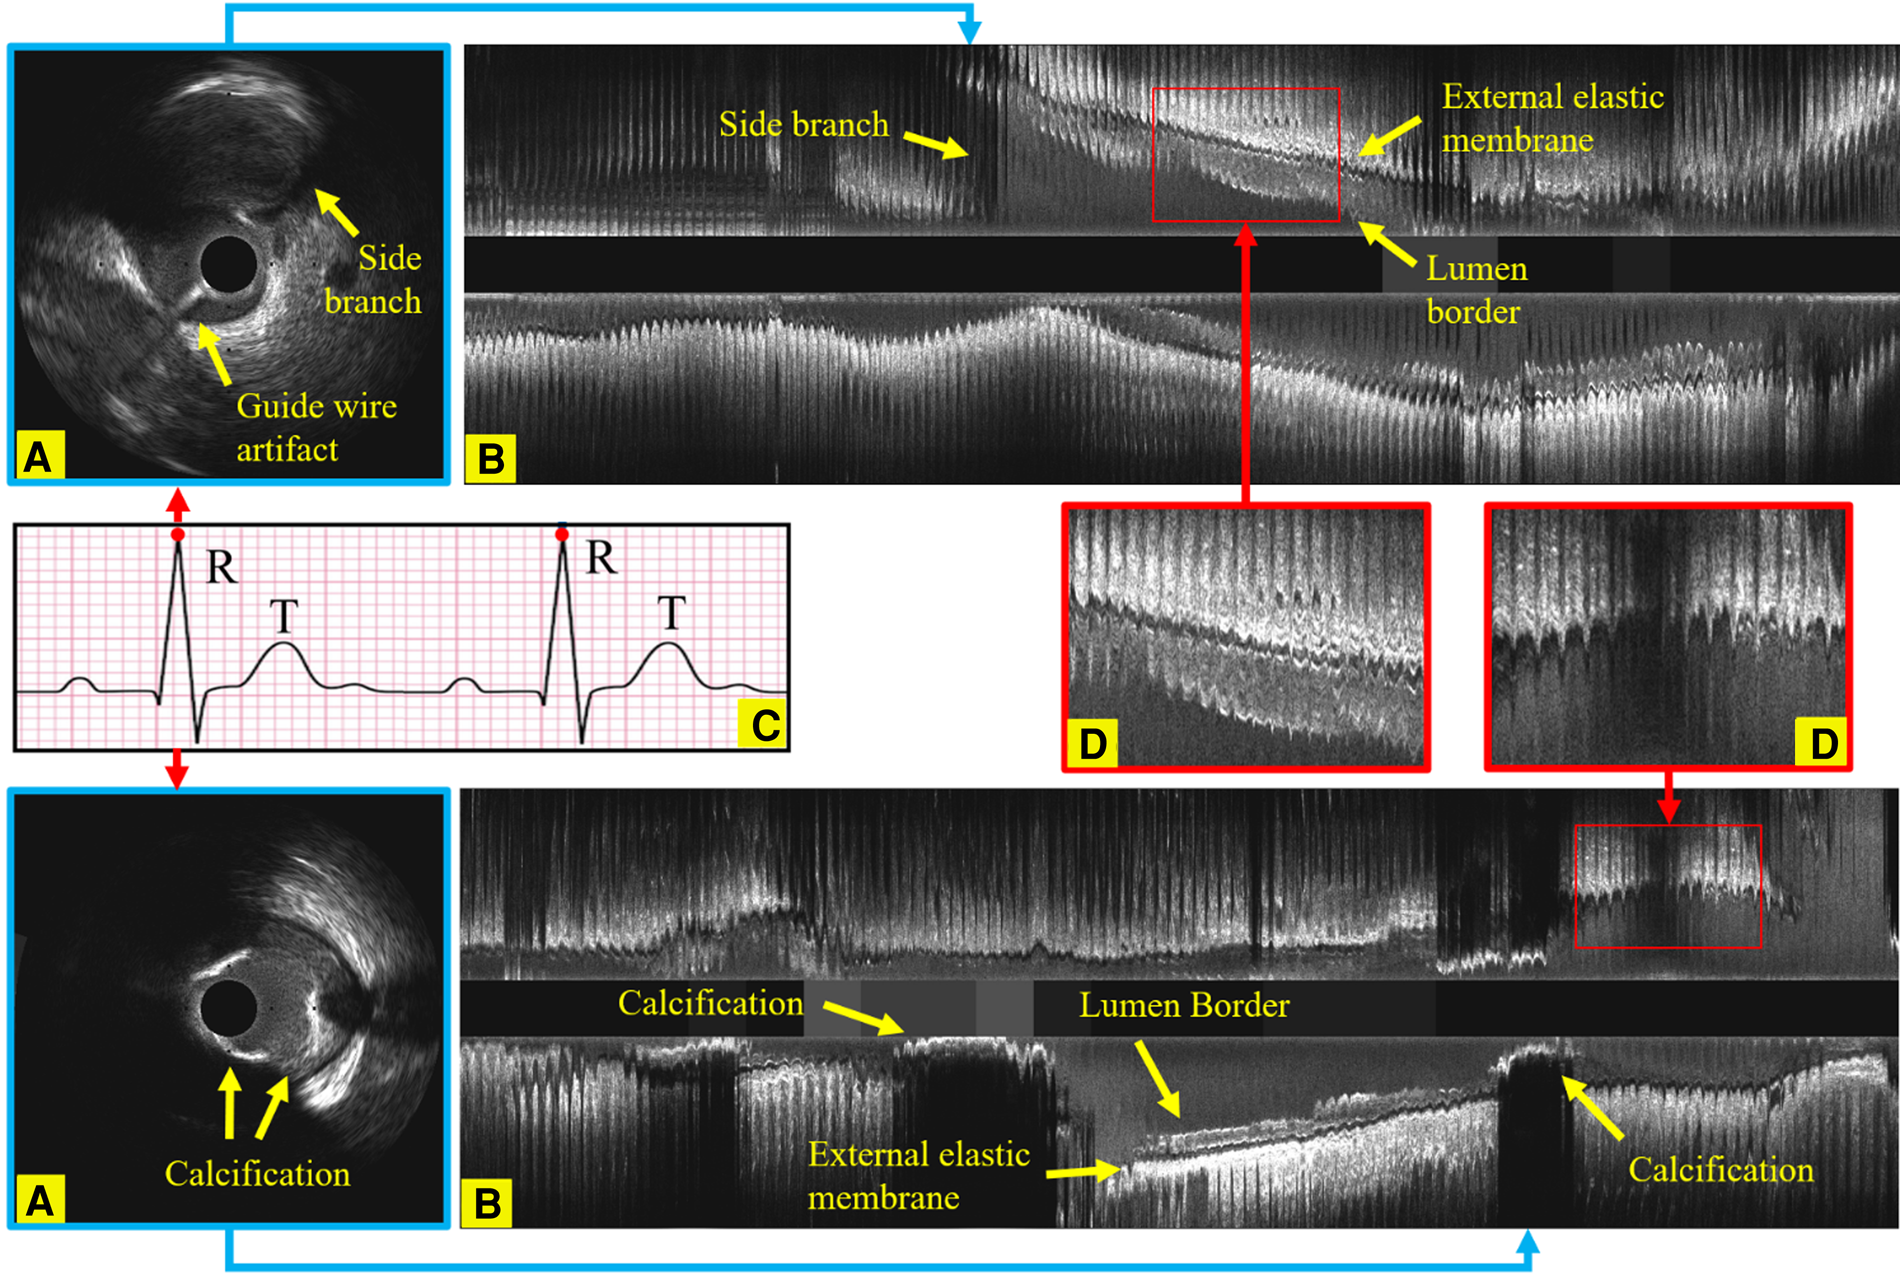

Intravascular ultrasound (IVUS) is the preferred modality to accurately assess lumen dimensions and coronary atheroma burden in clinical practice and in research studies, playing a pivotal role in diagnosing, treating, and monitoring coronary artery disease (CAD). In contemporary practice, IVUS image acquisition is performed using an automated pull-back device that withdraws the catheter at a constant speed without gating. However, the dynamic changes in luminal dimensions during the cardiac cycle can introduce significant variability, affecting the accuracy of volumetric analysis (1). Moreover, the IVUS catheter's movement in relation to the vessel during the cardiac cycle introduces additional errors in the quantification of atheroma volume (2). Recent reports have highlighted the superiority of IVUS volumetric analysis performed in end-diastolic (ED) frames, where cardiac motion is minimized, in providing more consistent and reproducible assessments of atheroma volume. Yet, the accurate detection of these ED-frames remains a challenge due to the intricate motion of the epicardial coronary arteries and the simultaneous motion of the IVUS catheter (3). Compounding this challenge are factors like noise, artifacts, and the complex imaging environment, which further hinder the correct identification of ED frames (4), as exemplified in Figure 1. Notably, even trained experts, despite their extensive experience, often struggle to consistently identify the ED-frames. Given these challenges, there's a pressing need for a fully automated, accurate, and reproducible method for ED-frame detection, which holds the promise of revolutionizing CAD management and treatment outcomes.

Figure 1

Longitudinal examples of an IVUS sequence, showing the side branches, the guide wire artifact and calcification, which all increase the challenges in identifying ED-frames. (A) An ED-frame. (B) The longitudinal view image of an IVUS pullback (3,000 frames). (C) An ECG signal. (D) Two enlarged longitudinal view images demonstrating the saw-tooth artery border caused by the movement of the vessel during the cardiac cycle.